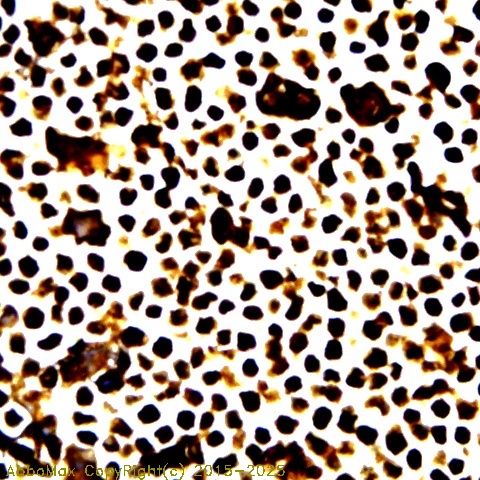

IHC

2-10 µg/ml